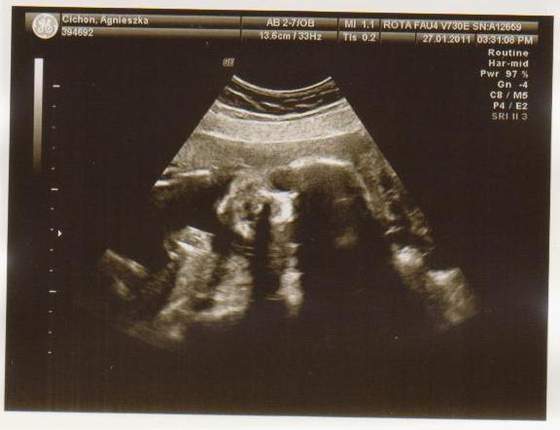

cześć dziewczyny to i ja chciałabym do Was dołączyć, właśnie znalazłam to forum. Mieszkam w Irlandii od 4 lat i mam synka 21 miesięcy, a teraz jestem w 28 tc bliźniaczej :-) dwie dziewczynki dwujajowe :-) też mnie trochę przeraża poród bliźniaków ale trzeba jakoś urodzić ;-) Pierwszy poród miałam jak marzenie szybko, sprawnie i nawet bez znieczulenia, mam nadzieję że i tym razem bęzie podobnie.

Hej podwojne mamunie:-)Ja juz rozpakowana dawno mamusia dubeltowka.Gratuluje wam serdecznie i witam w gronie tych wybranych hihiNiczego sie nie bojcie.Ciaxa blizniacza jest pod specjalna opieka.Czekaja was czeste wizyty w szpitalu i czeste ogladanie maluszkow na usg :-)